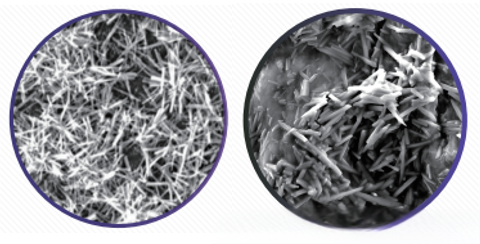

2)全新的药物晶体结构-微针晶:20um左右的微晶针结构的药物晶体,能够嵌入血管内壁中,减少血流冲刷脱落的概率,实现长期高药量的持续治疗靶病变;20um微晶针的设计除了长期留存以外,也是提高药物高转载的关键因素,另外还带来了安全性的好处,哪怕被血液冲刷下来了,也能快速分散溶解于血液,减少远端血管栓塞的发生;

图2;始祖鸟DCB微针晶药物结构图